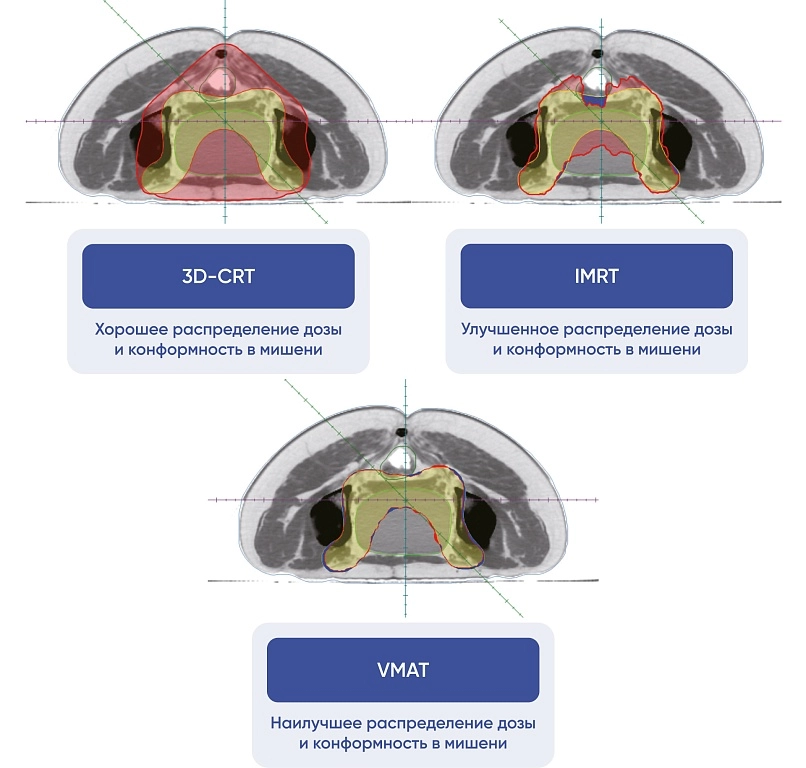

Методики лучевой терапии

- 3D-CRT: трехмерное конформное облучение;

- IMRT: облучение с изменением мощности дозы;

- VMAT: объемно-модулированная лучевая терапия;

Минимизирует лучевую нагрузку на здоровые ткани и органы риска.

Система планирования лечения TiGRT TPS с аппаратным ускорением (GPU) использует алгоритм Монте-Карло для быстрого расчета дозы терапевтического облучения. Поддерживает все виды лучевой терапии: 3D-CRT, IMRT, VMAT и SRS/SBRT.